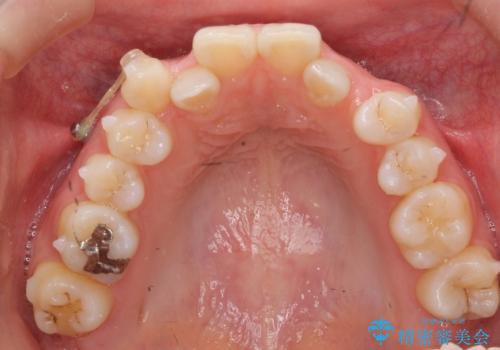

- 前歯のがたつきを主訴に来院。

左上の犬歯が歯肉退縮しており、そこを抜歯して矯正することにしました。

右上については、奥歯をインプラント矯正により後ろに動かして、引っ込んだ前歯を並べるスペースを確保しました。

右下6番については保存不可能であり、矯正治療終了後にインプラント補綴しています。